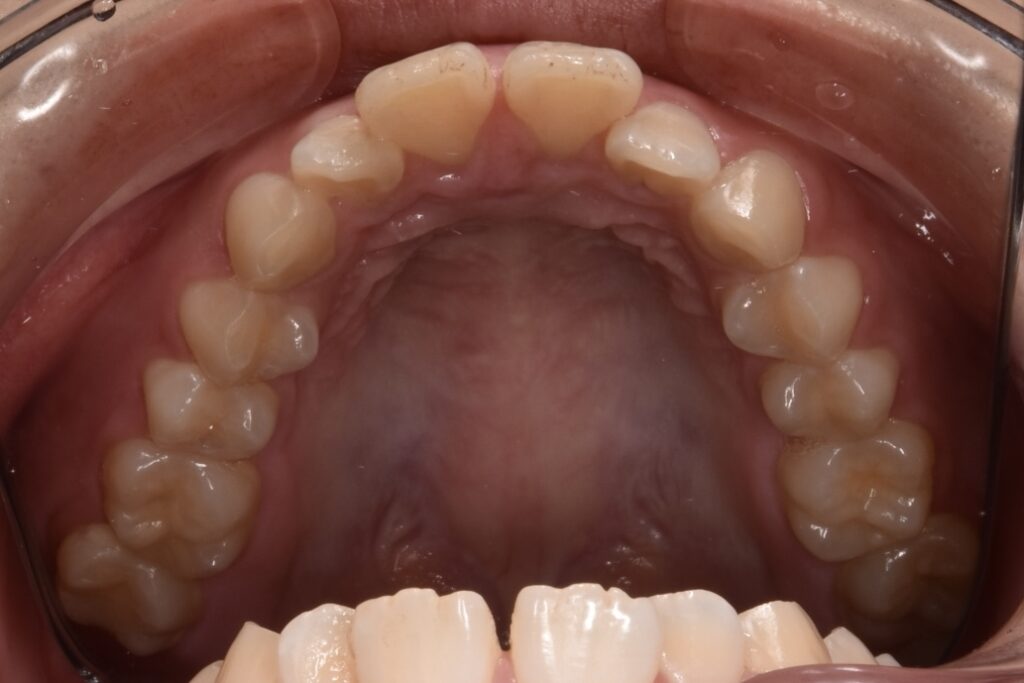

治療前